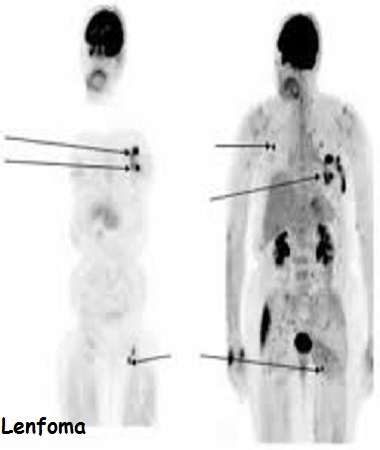

Sternum üzerinde biyopsi ile çıkarılmış melanom hastasında ameliyattan 2-3 saat önce Tc99 ile yapılan lenfosintigrafide her iki koltuk altında bekçi lenf bezlerinin görünür hale gelmesi.

Ad:  lenfoma.jpeg

Gösterim: 17668

Boyut:  43.1 KB